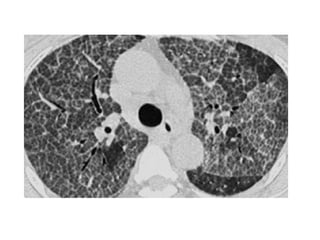

NSIP in a 53-year-old man with mild dyspnea, coronal CT image shows

diffuse lung involvement consisting of peripherally located irregular

linear opacities with ground-glass opacities (arrows), small cystic

lesions are seen (arrowhead)